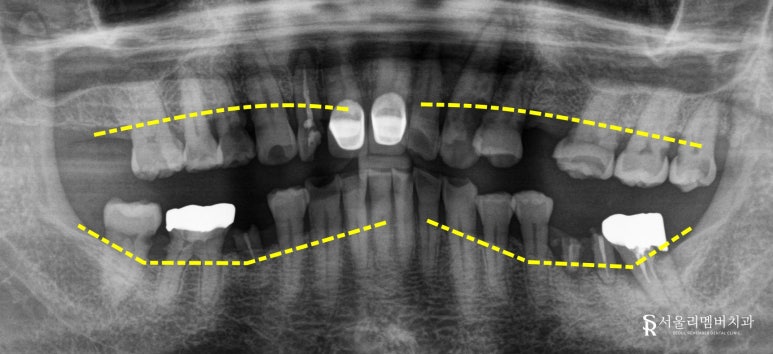

낙성대 치과 에서 파노라마 엑스레이를 보면

뿌리 염증뿐만 아니라

치조골까지 내려 앉아있는 모습을

확인할 수 있습니다.

전체적으로 치조골의 높이가

고르지 못하고

불규칙적으로 울퉁불퉁한 게 보이죠?

이는 자연치가 빠지고

오랜 시간 동안 그 자리가 채워지지 않아

치조골이 퇴축함과 동시에,

그나마 있던 치아들도

위생관리가 잘되지 않으니

잇몸이 내려앉기 때문에

일어난 현상입니다.

이렇게 치근을 잡고 있는

주변 조직들이 소실되면

당연히 치아는 흔들릴 수 밖에 없습니다.